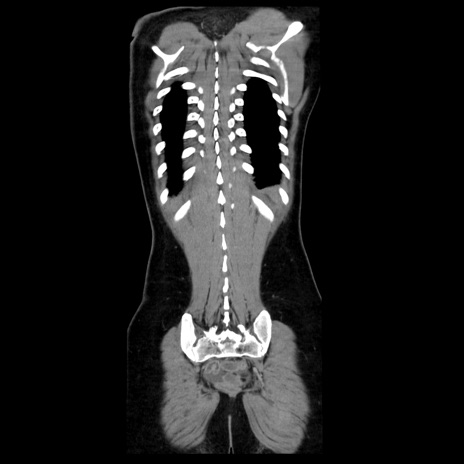

症例39(冠状断像)

【症例】40歳代女性

【主訴】上下腹部痛

【現病歴】2日目から下腹部痛あり。夜間は痛みで眠れなかった。昨日より上腹部痛と下痢が出現。臥位で痛みは軽快したため、休んでいた。本日になって臥位でも立位でも痛みが強くなってきたため救急要請。

【既往歴】子宮内膜症

【身体所見】部:平坦・軟、左上下腹部に圧痛あり、反跳痛あり。

【データ】WBC 21800、CRP 26.78

CT